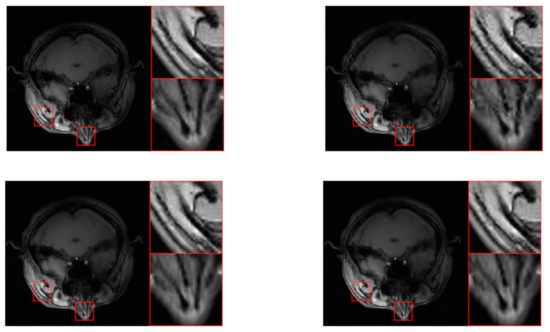

| “brain” | ||||||||||||

| SRD-DDTF | NLR-DDTF with | NLR-DDTF with | ||||||||||

| err | corr | psnr | time | err | corr | psnr | time | err | corr | psnr | time | |

| 15 | 23.87 | 95.51 | 28.73 | 476.95 | 22.87 | 95.88 | 29.10 | 909.44 | 22.50 | 96.02 | 29.24 | 1553.29 |

| 30 | 15.57 | 98.12 | 32.44 | 944.79 | 12.34 | 98.82 | 34.46 | 1284.81 | 12.09 | 98.87 | 34.63 | 2059.53 |

| 45 | 12.97 | 98.70 | 34.03 | 1390.10 | 9.31 | 99.33 | 36.91 | 1728.38 | 9.22 | 99.34 | 36.99 | 2453.39 |

| 60 | 11.60 | 98.96 | 35.00 | 1777.77 | 7.51 | 99.56 | 38.77 | 2112.93 | 7.45 | 99.57 | 38.84 | 2838.36 |